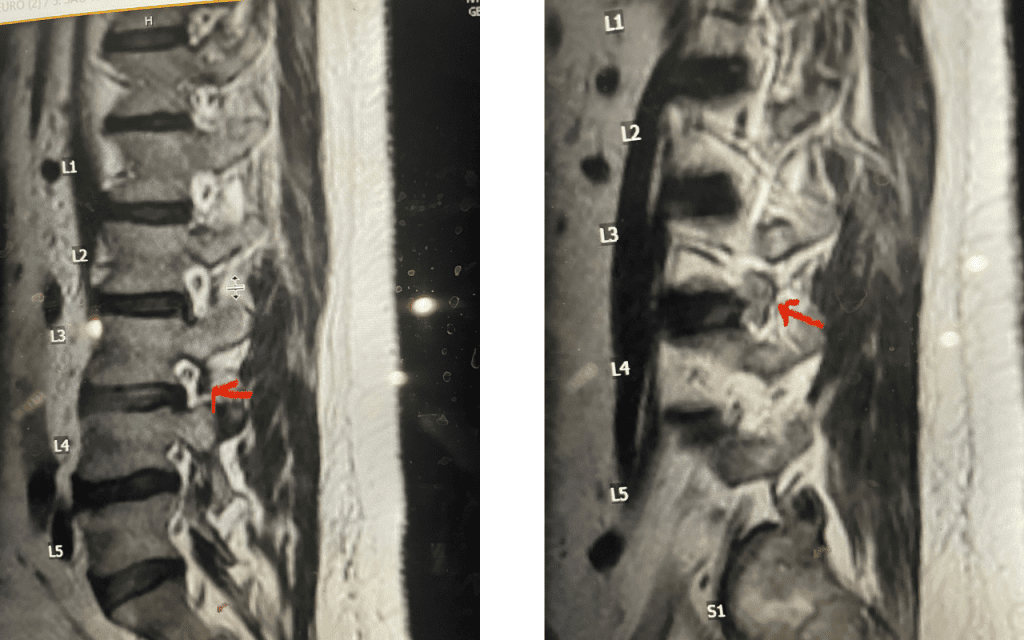

Fig 9: Axial and Sagittal T2-weighted lumbar MRI demonstrating left L4-5 far lateral disc herniation (red arrow). Notice how on the sagittal MRI the disc herniation fills the foramen and is superiorly oriented, compressing the left L4 nerve root against the L4 pedicle (blue arrow).

We had a recent flurry of lateral disc herniations. Another challenging case recently was a 76-year-old male who presented with 6 weeks of severe left anterior thigh pain, numbness, and weakness of his hip flexor and quadriceps, four years prior at L4-5 he had a removal of a large L4-5 synovial cyst on the right side of the canal and in situ fusion for which he had done very well. New imaging about a month prior revealed a new large far lateral disc herniation on the left side (Fig 9). The patient had mild spinal stenosis at this level and the cyst gone, but the disc on the left was extraforaminal at L4-5 compressing the left L4 nerve root. He had a trace spondylolisthesis. The patient underwent a series of epidurals with no improvement. Patient agreed to proceed with surgery. The laterality of the disc fragment made it amenable in our opinion for a lateral approach as to attempt a medial approach would be quite risky given the prior laminectomy and attendant scar formation which would increase risk for spinal fluid leak. The prior fusion mass was thin and incomplete and was removed easily with Kerrison punch. The main problem was the scarring in the intertransverse space and discerning the anatomy of the L4-5 facet complex. However, we remained in the “safe zone” and although the nerve was buried in scar tissue was not well identified, we were able to dissect enough to extract the disc fragment. This fragment was clearly pushing upward the scar tissue containing the L4 nerve root. We added an in-situ fusion with BMP because of the slight spondylolisthesis although we had to remove a minimal amount of bone in the safe zone for exposure. Fortunately, the patient had relief from his symptoms.